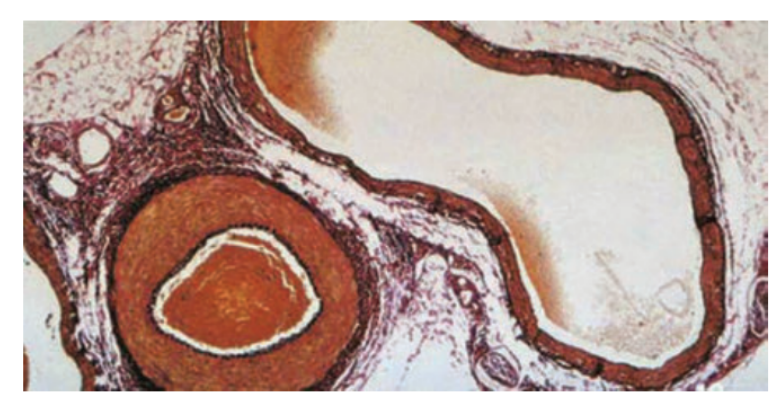

🔴 Arteries

- Function → carry blood away from heart (mostly oxygenated, except pulmonary artery).

- Wall: very thick, muscular & elastic → withstands and maintains high pressure.

- Lumen: narrow (smaller diameter) → keeps blood under pressure.

- Valves: absent (pressure is already high, prevents backflow).

- Adaptation → Elastic fibres stretch + recoil with each heartbeat → maintains a pressure wave (pulse).

🔵 Veins

- Function → carry blood back to heart (mostly deoxygenated, except pulmonary vein).

- Wall: thin, with little muscle & elastic tissue → blood pressure is low.

- Lumen: wide → reduces resistance, helps smooth flow.

- Valves: present → prevent backflow (important because pressure is low).

- Adaptation → Movement of body muscles squeezes veins → valves ensure one-way flow toward heart.